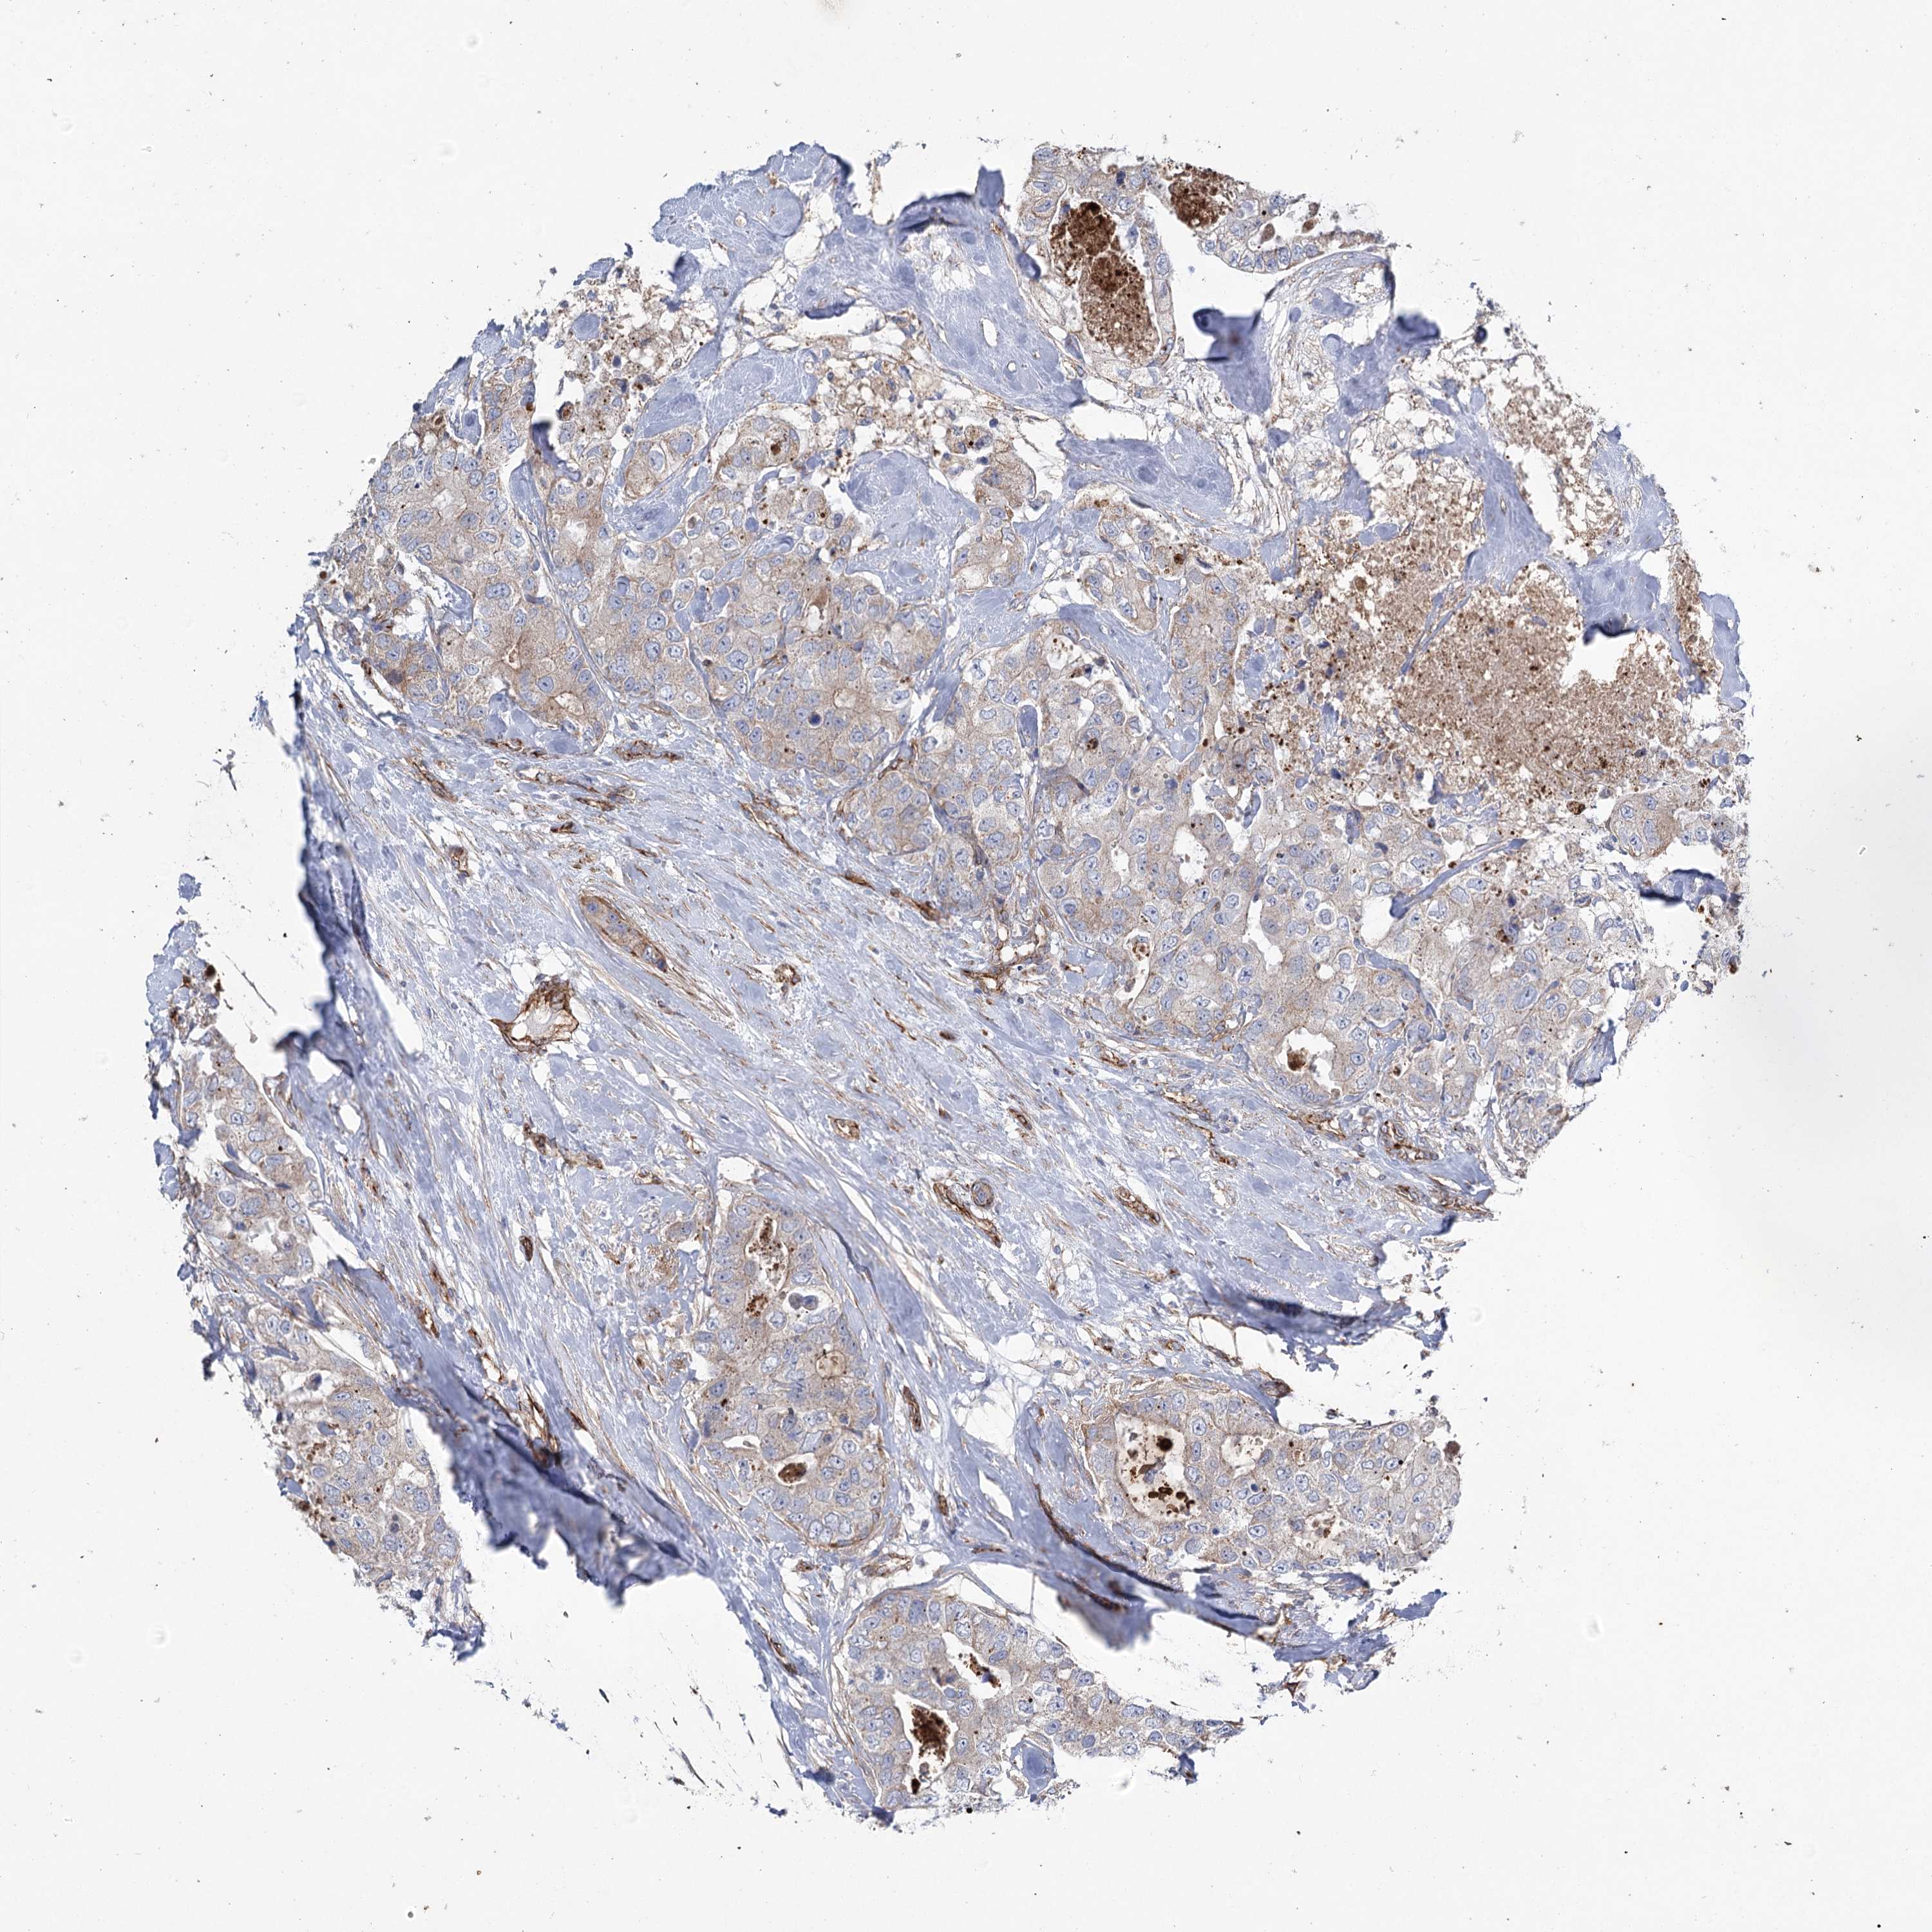

CANCER BREAST CANCER Show tissue menu

BRCA TCGA BRCA VALIDATION PROTEIN EXPRESSION

Breast cancer

Human cancer

Breast invasive carcinoma